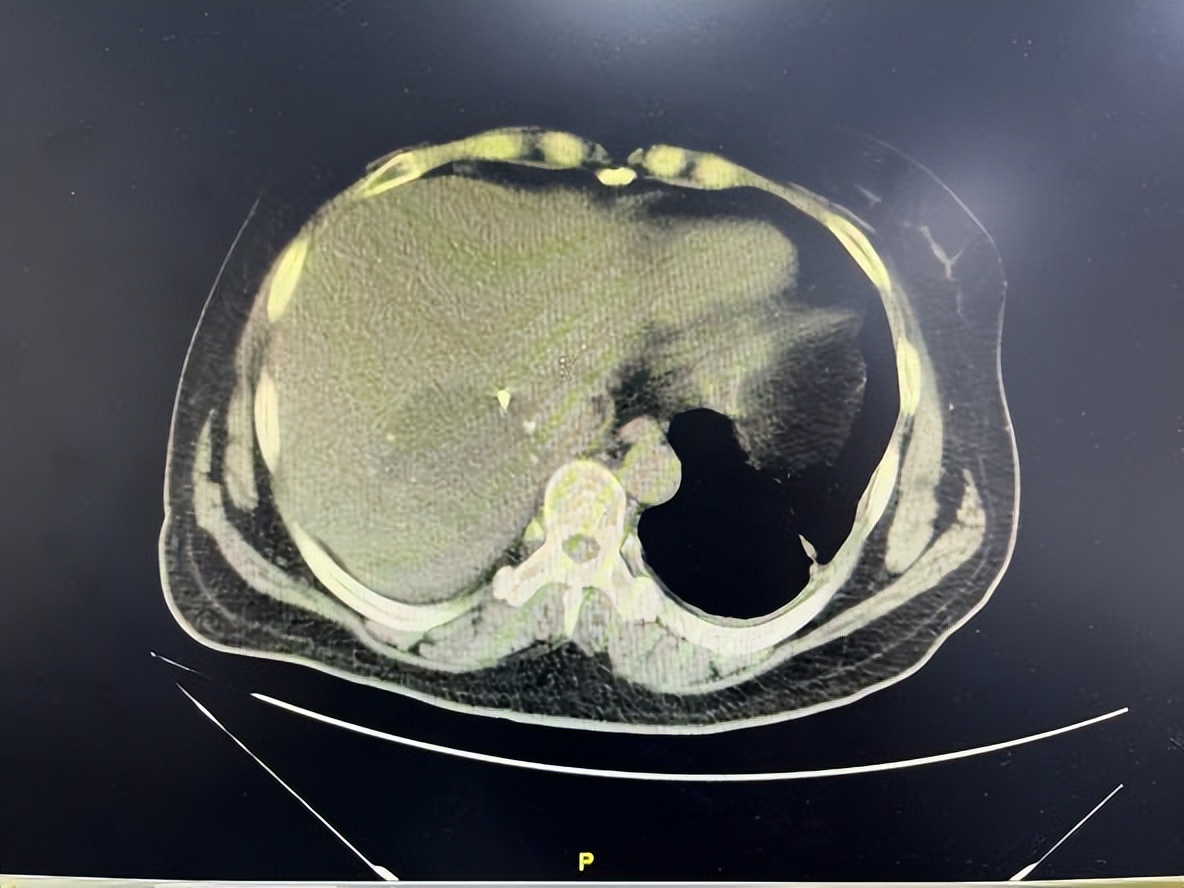

本着一切为了患者的信念,陆朝阳教授团队通过术前 3D立体成像技术精确评估,反复推敲设计手术路径,通过术中超声定位,最终在腹部超声科、麻醉科、手术室、护理等团队的合作下,经5小时的奋战,依靠成熟的微创手术技术和丰富的手术经验,仅仅通过腹壁上的6个小孔就实现了腹腔镜下巨大肝血管瘤的微创切除,整个手术出血量不到100ml。术后12小时患者恢复进食,仅36小时就可下地活动, 患者术后各项指标恢复良好,术后5天康复出院。

▲图 2 术前、术后复查CT对比提示肝脏恢复良好